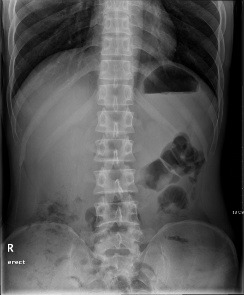

전반적인 복부의 전처치 상태, Liver, Spleen, Kidney, Stomach등의 크기와 형태 및

Calcification이나 Mass등의 유무를 관찰 한다.

Iliac Crest 에서 위로 5~7cm지점에 수직입사

14 " X 17 "

환자는 가능한 Erect Position을 취한다.

AP Position에서 몸무게를 양발에 균등 분배 시키고 양 어깨를 동일 횡단면에 놓고

양팔이 Cassette에 닿지 않도록 약간 벌린다.

치골 결합에서 상복부까지 포함 시켜야 한다.

척주는 사진의 중앙에 있어야 한다.

늑골, 골반, 사진의 양측 가장자리에서 똑같은 자리에 있어야 한다.